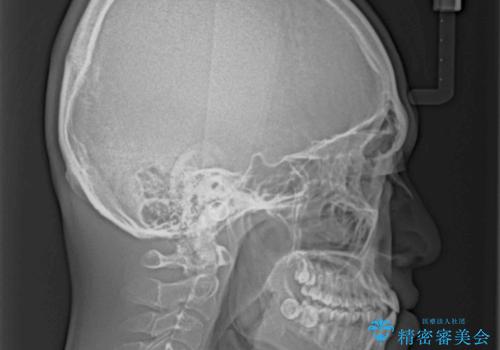

受け口傾向の骨格であり、前歯はクロスバイトまたは切端咬合となっており、叢生は警備であったため、下顎を中心に歯列全体の後方移動を行い、IPR(歯と歯の間を削る)によってデコボコが解消するように設計し、インビザラインにより治療を行うこととしました。

受け口傾向のインビザライン矯正は比較的治療を行いやすいため、きれいに仕上げることができました。舌の突出癖が顕著であったため、改善のためのトレーニングをしっかりと行っていただきました。